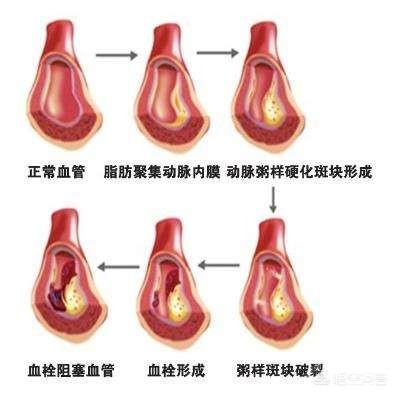

La plaque la plus grave est la plaque cardiovasculaire, ou plaque carotidienne, dont l'aggravation entraîne une ischémie myocardique, une ischémie cérébrale ; si elle n'est pas activement contrôlée, la plaque peut même se rompre et se thromboser, entraînant un infarctus du myocarde ou un infarctus cérébral.

Sous l'influence de facteurs de risque cardiovasculaire tels que l'hyperlipidémie, la paroi interne des vaisseaux sanguins est progressivement endommagée et les lipides en excès dans le sang se déposent progressivement sous la paroi du vaisseau, formant un noyau lipidique athéromateux jaune, et finalement une chape fibreuse se forme dans le noyau lipidique, ce qui constitue le processus de formation de la plaque artérielle. La plaque est un facteur de risque conduisant à l'athérosclérose, et les plaques qui ont des problèmes de stabilité et se rompent peuvent conduire à une agrégation plaquettaire réactive. L'agrégation réactive des plaquettes peut même conduire à la formation de caillots sanguins, bloquant les vaisseaux artériels et provoquant des maladies cardiovasculaires infarciques. Ce qu'il faut faire, c'est prévenir la formation de la plaque par des médicaments et des exercices raisonnables, essayer de maintenir la stabilité de la plaque existante, ralentir le processus d'athérosclérose et empêcher la rupture de la plaque d'entraîner un risque plus élevé.

La plaque a la plaque veineuse, la plaque artérielle, c'est dans le rôle de multiples facteurs étiologiques, en raison de la lipidation de la précipitation, pour dire les choses franchement, c'est-à-dire, vous graissez plus, la digestion et l'utilisation ne peut pas être, dans les lipides sanguins quatre et d'autres facteurs multiples sous l'influence de et puis des dommages à l'intima, le dépôt à la couche interne des vaisseaux sanguins, la formation d'un noyau lipidique jaune athéromateux, et finalement dans la formation d'un noyau fibreux sur le noyau lipidique, qui est normalement très stable, si la coiffe fibreuse est soumise à une inflammation soutenue. la chape fibreuse se rompt, la plaque s'écoule et les plaquettes sanguines dans le mariage éclair donnent naissance à un enfant perturbateur, appelé thrombus, qui se promène pour semer le trouble, se spécialise dans les mauvaises actions pour bloquer les vaisseaux sanguins, le thrombus dans la lumière des vaisseaux sanguins devient plus étroit en même temps, mais aussi se rompt, déclenchant des événements vasculaires cardio-cérébraux et cérébraux aigus, tels que l'accident vasculaire cérébral, l'infarctus du myocarde, l'embolie pulmonaire, l'insuffisance rénale, les veines variqueuses, etc. etc. Par conséquent, l'élimination de la plaque ne permet pas seulement de déboucher les vaisseaux sanguins, mais aussi de prévenir les accidents cardiovasculaires et cérébrovasculaires aigus, ce qui est dans l'esprit de tout le monde.

La plaque artérielle est une série de réactions inflammatoires déclenchées par des lésions de la paroi artérielle sous l'effet de multiples facteurs étiologiques, avec la formation ultérieure d'une plaque athéromateuse secondaire. La formation de la plaque est plus nocive pour le corps humain, elle rétrécit la lumière du vaisseau sanguin en même temps, elle peut aussi se rompre, déclenchant des événements cardiovasculaires aigus, par conséquent, l'élimination de la plaque non seulement débouche le vaisseau sanguin, mais prévient également les événements cardiovasculaires aigus, qui sont le battement de cœur de tous les patients. Pour le traitement de la plaque, nous pouvons commencer par la cause de la maladie, comme le contrôle des lipides sanguins, de la tension artérielle, de la glycémie, etc., ainsi que le changement d'un mauvais mode de vie, comme un régime pauvre en sel et en cholestérol, l'augmentation de l'exercice, l'arrêt du tabac et la limitation de l'alcool, etc. ou, en plus du traitement ci-dessus, nous pouvons donner des médicaments, et le choix du médicament est la statine, comme l'atorvastatine, la reserpulvastatine et ainsi de suite sont couramment utilisés dans le traitement des plaques d'athérome, et le choix exact du traitement doit être formulé sous la direction d'un médecin spécialiste. Le choix exact du traitement doit être formulé sous la direction d'un médecin spécialiste. Le plan de traitement spécifique doit être formulé sous la direction de médecins spécialistes.

Cependant, même lorsque ces traitements sont administrés, la plaque artérielle est difficile à éliminer. De nombreux patients ont entendu dire que les statines pouvaient inverser la plaque, mais par inverser la plaque, nous entendons transloquer les lipides hors de la plaque, réduire la plaque d'athérome, augmenter sa stabilité, réduire le risque de rupture et diminuer le risque d'événements cardiovasculaires, et non pas éliminer complètement la plaque du vaisseau sanguin, pour ainsi dire, et une fois que la plaque est formée, il est presque impossible de l'enlever.

La matière lipidique d'un point faible peut se nécroser avec le temps, tout comme une infection cutanée devient fibrotique et croûteuse lorsqu'elle se remplit de pus, ou la calcification se produit lorsqu'il y a des dépôts de calcium, que la plaque se durcit et que la fonction vasoconstrictrice des vaisseaux sanguins est davantage compromise ; ces plaques sont appelées des points durs.

Les plaques précoces peuvent ne pas avoir gravement endommagé la structure des vaisseaux sanguins et il est possible qu'elles puissent être éliminées et inversées, tandis que les plaques molles et les plaques dures ont déjà remplacé la structure normale des vaisseaux sanguins. Il est impossible de les éliminer complètement, et ce qu'il faut faire, c'est arrêter et ralentir la croissance continue des plaques.